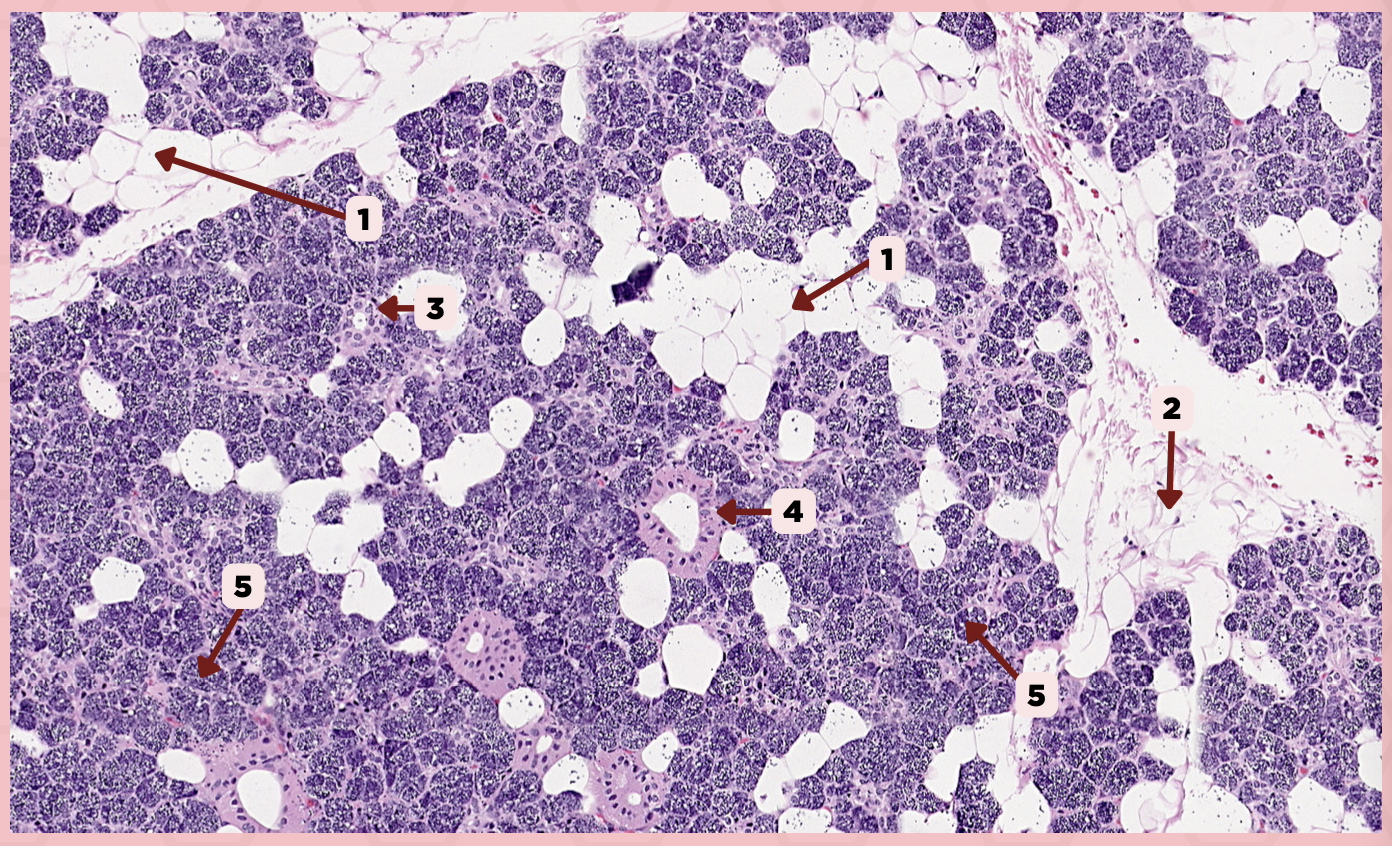

Parotid

Identify the specimen.

Capsule

Identify the structure labeled as 1.

Septa

Identify the structure labeled as 2.

Lobule

Identify the structure labeled as 3.

Lymph Node

Identify the structure labeled as 4.